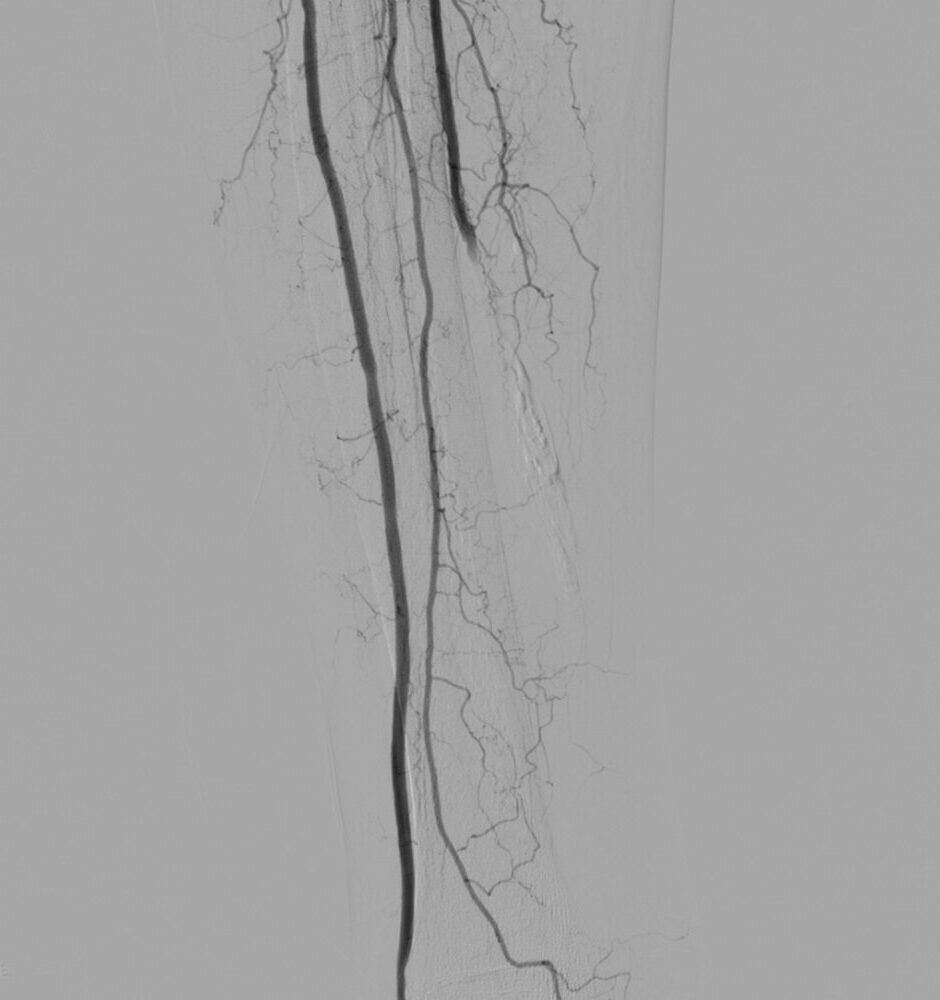

Endovascular treatment of infrapopliteal lesions has become more common and techniques continue to improve, Vascular Specialists are exploring use of endovascular therapy in more distal arterial territories.

The pedal loop technique, allows for intervention on the distal tibial arteries and the pedal/plantar loop while only using one access site which can improve transcutaneous oxygen tension in the foot at 15 days.  The angiosome concept has gained popularity as an approach to improve limb salvage, whereby the target vessels for revascularization are chosen based on the angiosome in which the wound is located. The limb salvage was 86% when wound angiosomes were directly revascularized versus 69% for indirect revascuarlization.

Treatment options in Endovascular Surgery are Infrapopliteal Angioplasty, Infrapopliteal Angioplasty and Stenting, Drug-Eluting Stents, Excisional atherectomy. These techniques mentioned above are deployed appropriately to get the best outcomes for limb salvage.

PREOPERATIVE ASSESSMENT AND PREOPERATIVE IMAGING with Duplex scan of lower limb arterial system,CT angiogram and In most patients, standard arteriography is still the “gold standard. If endoluminal therapy is the case, Endoluminal/Endo Vascular treatment at the time of diagnostic arteriography is  performed.